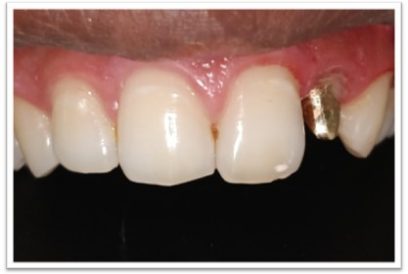

Patient Name:Anil Jagtap

Tooth Involved : 22

Diagnosis : Ellis Class IV Fracture With 22

Treatment : Root Canal Treatment 22

Restoration: Cast Post And Core With Porcelain Fused To Metal Crown.

Before